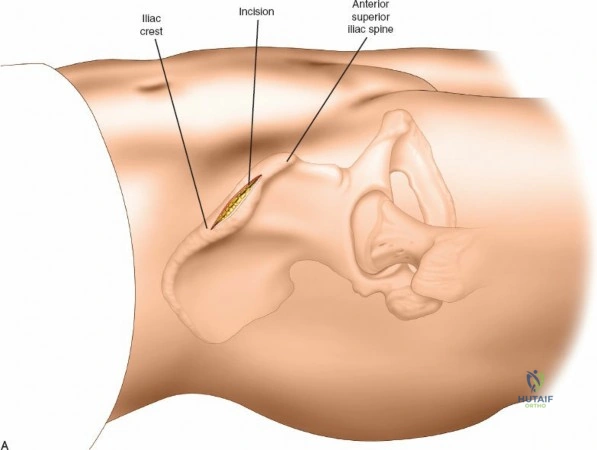

Wrist Spanning External Fixation

Wrist spanning fixators are the workhorse for highly comminuted distal radius fractures or radiocarpal fracture-dislocations.

Metacarpal Pin Placement

1. Make two 1 cm incisions over the dorsoradial aspect of the second metacarpal.

2. Dissect bluntly, protecting the dorsal sensory branches of the radial nerve and the extensor tendons.

3. Place the tissue sleeve at a 45-degree angle to the dorsal and lateral planes to maximize purchase in the metacarpal shaft.

4. Pre-drill and insert two 3.0 mm pins.

Proximal Radius Pin Placement

1. Make incisions over the dorsolateral aspect of the radius, approximately 10-12 cm proximal to the radiocarpal joint.

2. Dissect bluntly to avoid the SRN.

3. Insert two 4.0 mm pins.

Construct Assembly and Reduction

Connect the metacarpal pins and the radius pins with a multi-pin clamp or individual pin-to-bar clamps. Apply longitudinal traction to utilize ligamentotaxis to restore radial length and radial inclination. Volar tilt is often restored by translating the distal fragment or applying a slight volar directed force before tightening the frame. Confirm reduction with PA and lateral fluoroscopy.